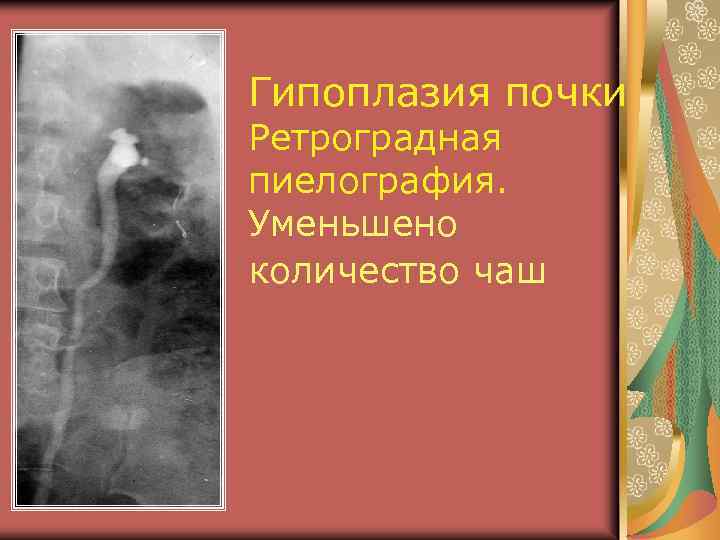

Аномалии величины Гипоплазия почки (0, 2%) Нормально сформированный орган маленьких размеров Причина – аномалия сосудов, аномалия закладки метанефроса Функция не нарушена Дифференциальный диагноз с первично и вторично сморщенной почкой

УЗ признаки гипоплазии Все размеры почки равномерно уменьшены. Объем меньше нормальной почки на 30% Структура почки обычная Контуры четкие, капсула прослеживается Дифференциация между паренхимой и срединным эхокомплексом и кортикомедуллярная дифференциация сохранены

Гипоплазия почки – 0, 2% Размеры уменьшены Структура сохранена Контуры гладкие

УЗИ – гипоплазия правой почки

Гипоплазия почки

Гипоплазия почки

УЗИ – гипоплазия правой почки?

Гипоплазия почки Ретроградная пиелография. Уменьшено количество чаш